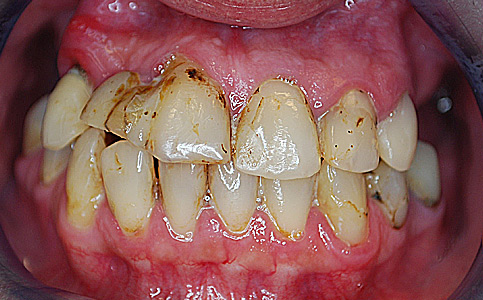

Przykład pełnej rehabilitacji protetycznej obejmujący leczenie biologiczne, uzupełnienie braków zębowych implantami oraz korony pełnoceramiczne w łuku górnym i dolnym. Spektakularna metamorfoza uśmiechu wykonana przez zespół Centrum Stomatologii i Ortodoncji FRESHmed odmieniła życie Pacjenta dodała pewności siebie i sprawiła, że z chęcią się uśmiecha.